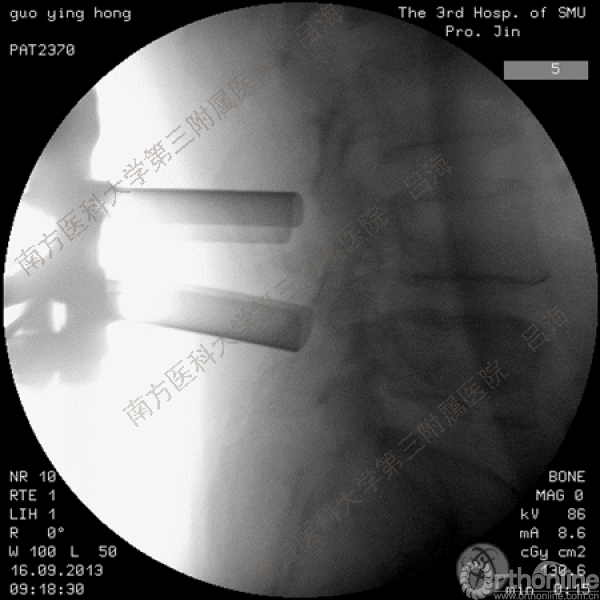

随着社会老龄化进程加快,胸腰椎退行性病变的治疗已经成为脊柱学术界的一个热点话题。MIS-TLIF手术可以治疗多种不同的胸腰椎退行性疾病,南方医科大学第三附属医院吕海教授结合病例为我们一一展示了该术式在治疗不同胸腰椎疾病时的具体手术过程。